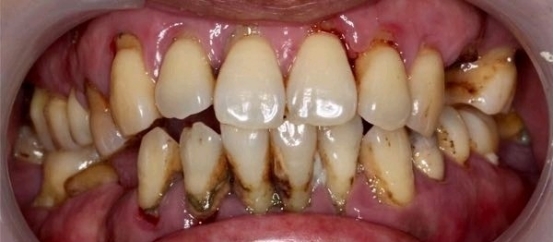

重度牙周炎的示意图

牙周病导致牙龈萎缩、牙根暴露,甚至牙齿松动

经过牙周治疗以后,牙周炎得以控制